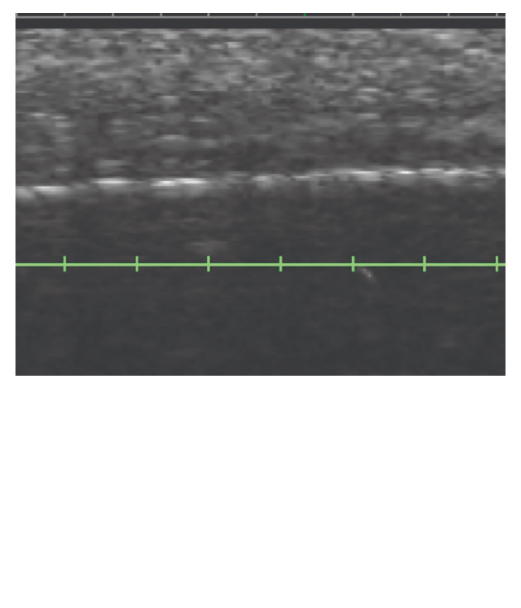

超音波影像

專利DeepSEETM智能超音波影像技術,判斷肌膚治療層次

即時監測,精準傳遞音波能量,療程更安全高效